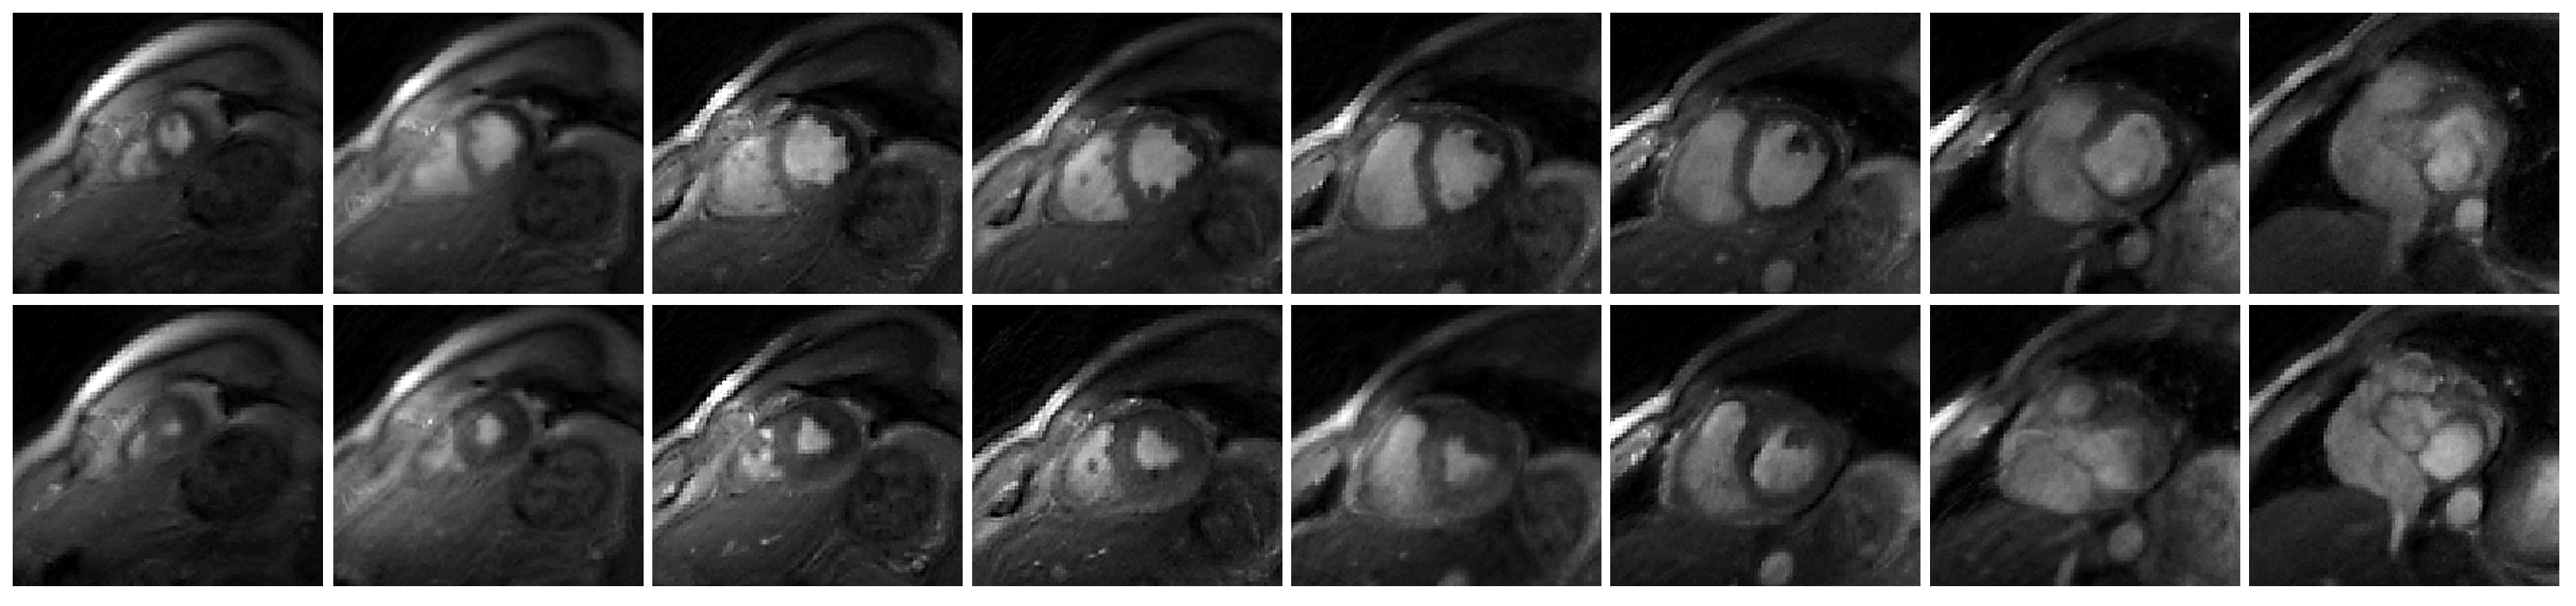

In Figure 4, we showed the visual comparison of the reconstructed free-breathing images and the fully-sampled breath-hold images acquired using the bSSFP sequence. The slices shown in Figure 4 were from Subject #4. Figure 5 was the visual comparison of the reconstructed free-breathing images and the fully-sampled breath-hold images acquired using the FGRE sequence. We reconstructed the whole time series, and we randomly chose a cardiac cycle (from end-systolic to end-diastolic) for comparison with the breath-hold cine.

Figure 4.

Visual comparison of the reconstructed free-breathing images and the fully-sampled breath-hold images. End-systolic and end-diastolic phases from six slices are shown in the figure. The six slices are from Subject #4. We note that the free-breathing images are acquired using the GRE sequence and the fully-sampled breath-hold images are acquired using the bSSFP sequence. This results in different contrast between the two types of the images.